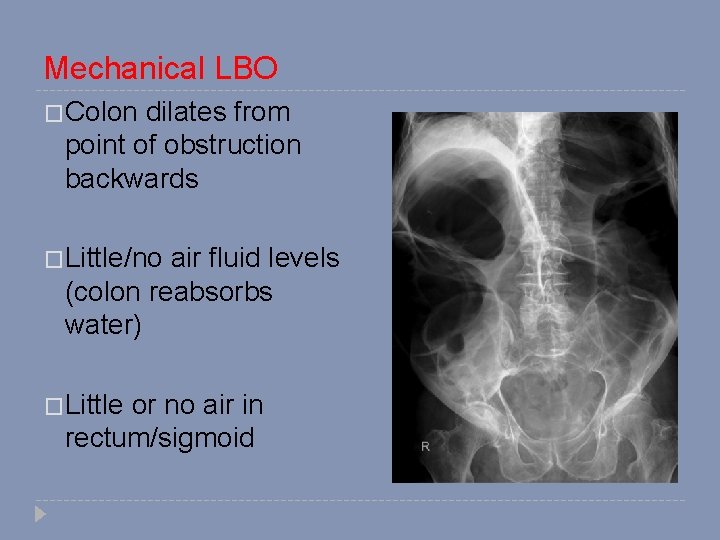

Mechanical LBO �Colon dilates from point of obstruction backwards �Little/no air fluid levels (colon reabsorbs water) �Little or no air in rectum/sigmoid